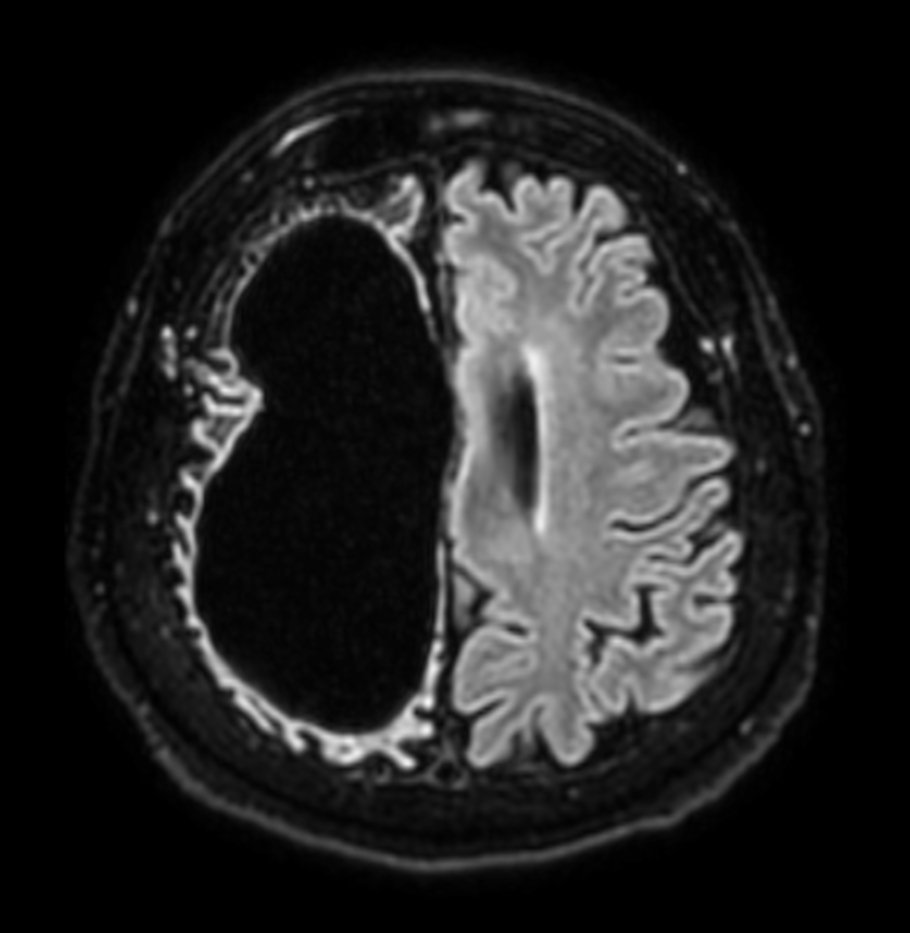

Axial T2w FFE